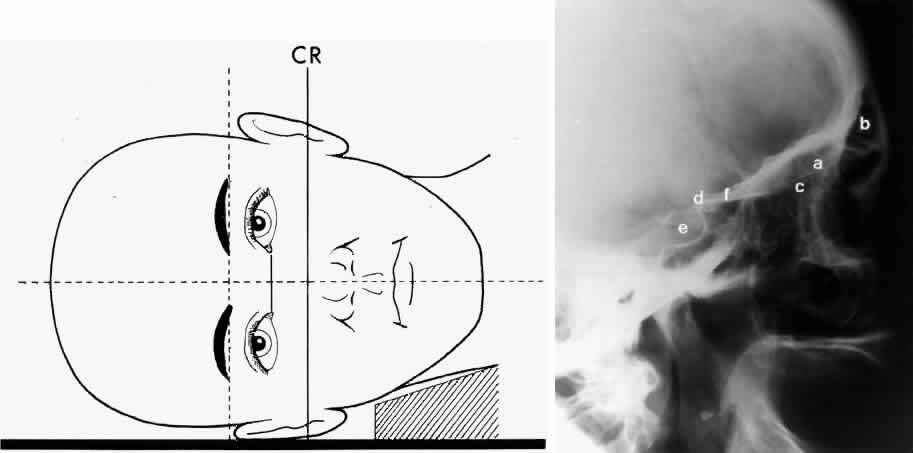

OPTIC FORAMEN (RHESE POSITION)

In 1911 Rhese14 described a projection (Fig. 6) for the evaluation of the ethmoid sinuses and the optic foramen. The patient is positioned with the orbit to be studied against the x-ray cassette. The zygoma, nose, and chin should touch the cassette. The x-ray beam is directed posterior-anteriorly at 40 degrees to the midsagittal plane.5,6 In this position the optic canal is in the inferolateral quadrant of the orbit and oriented perpendicular to the x-ray cassette.15 Variations of this standard position can be used to view other structures of interest. The Rhese projection allows assessment of the orbital apex, in particular, the optic foramen, optic strut, and the upper ethmoid sinus. A pneumatized anterior clinoid process may simulate the optic foramen. The landmark for finding the foramen is to find the planum sphenoidale; the optic foramen lies at its lateral end. The optic canal may be evaluated for expansion or compression by disease processes, such as optic nerve tumors (glioma and meningioma) and trauma. CT and magnetic resonance imaging show much better detail and therefore have replaced the use of plain films for evaluation of the optic canal.

Fig. 6. A and B. Schematic showing positioning for an oblique apical projection (Rhese position). (CR, central ray; CM, canthomeatal line) C. Radiograph of an oblique apical projection. (a, right optic canal; b, optic strut; c, superior orbital fissure; d, ethmoid sinus; e, planum sphenoidale; f, greater wing of sphenoid) (A and B; Rao VM, Gonzalez CF: Plain film radiography and polytomography of the orbit. In Gonzalez CF, Becker MH, Flanagan JC [eds]: Diagnostic Imaging in Ophthalmology, pp 1–7. New York, Springer Verlag, 1986)